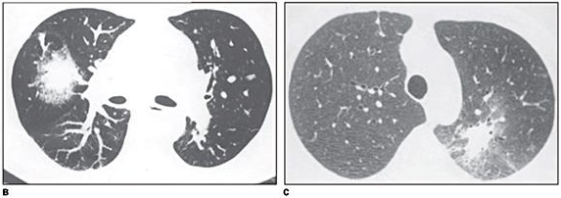

Homem de 25 anos, em tratamento quimioterápico para leucemia T aguda, interna

na UTI por SDRA, necessitando de suporte ventilatório invasivo. A contagem de neutrófilos totais é de

1.045/mL. Foi realizada uma TC de tórax, demonstrada abaixo:

Qual o diagnóstico provável e a causa da imunossupressão do paciente?